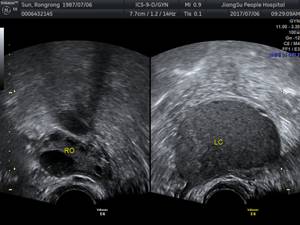

B超:主要对卵巢巧克力囊肿的诊断有价值,典型的超声影像为无回声区内有密集光点(即所谓的“泥沙样”回声)。(下图)

图:RO为右侧正常卵巢;LC为左卵巢巧囊